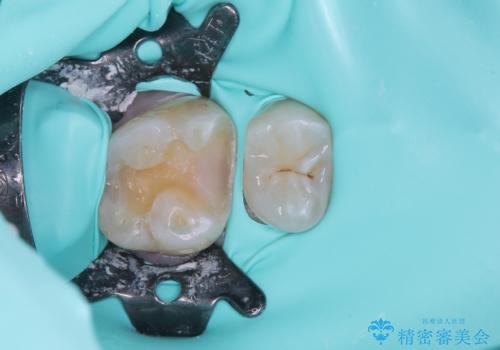

セラミックインレーを接着する際は、ラバーダム防湿を行いました。

精度の高い詰め物は、二次う蝕になりにくいです。